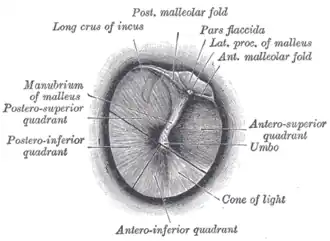

Existem duas regiões gerais da membrana timpânica: a paridade flácida (região superior, ver imagem à direita) e a paridade tensa. As paridade flácidas consistem em duas camadas, é relativamente frágil, e está associada com a disfunção da trompa de Eustáquio e colesteatomas. As maiores regiões da paridade tensa consiste em três camadas: pele, tecido fibroso, e a mucosa. É relativamente robusto, e é a região mais comumente associada com perfurações.[3]

Membrana timpânica direita. | |